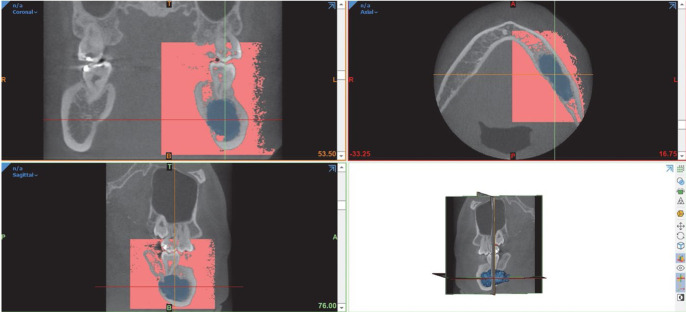

目的:本研究旨在利用锥束计算机断层扫描(CBCT)进行三维容积分析,探讨影响牙源性囊肿减压术后缩小率的潜在因素:研究样本包括 2010 年至 2022 年期间在朱拉隆功大学牙科学院口腔颌面外科接受牙源性囊肿减压术的 41 名患者的 CBCT 图像。研究人员收集了术前和术后的 CBCT 结果,并进行了体积分析,以评估基于不同参数的囊肿病变缩小率和体积缩小百分比的差异。对这些参数之间的相关性进行了分析,以确定其关联性:结果:在这项研究中,牙源性囊肿的平均减压时间为 316 天。男性的减压率高于女性(PPC结论:对牙源性囊肿减压率的了解可以帮助我们更好地了解牙源性囊肿:了解牙源性囊肿的缩小率对于外科医生评估去核手术前的减压时间和确定最终治疗方案至关重要。性别和初始病变体积对缩小率有显著影响。

Purpose: This study aimed to investigate the potential factors that could affect the reduction rate of odontogenic cysts following decompression using cone-beam computed tomography (CBCT) for 3-dimensional volumetric analysis.

Materials and methods: The study sample consisted of CBCT images of 41 individuals who underwent decompression of odontogenic cysts at the Department of Oral and Maxillofacial Surgery, Faculty of Dentistry, Chulalongkorn University, between 2010 and 2022. Preoperative and postoperative CBCT results were collected, and a volumetric analysis was conducted to evaluate the differences in the reduction rate and the percentage of volume reduction of cystic lesions based on different parameters. Correlations between these parameters were analyzed to determine associations.